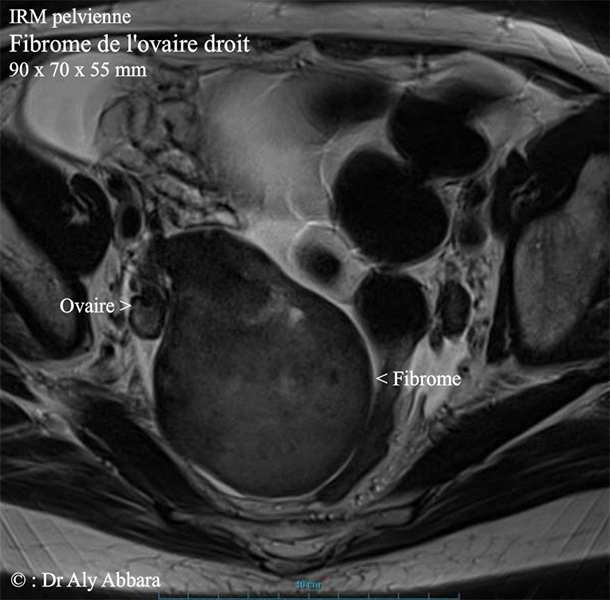

Fibrome de l'ovaire droit - IRM

Fibrome de l'ovaire droit - image obtenue par IRM (imagerie par résonance magnétique).

Il s'agit d'une tumeur ovarien de 90 x 70 x 55 mm de dimensions (soit environ 180 cm3 de volume).

L'examen anatomopathologique confirme sa nature : fibrome bénin de l'ovaire.

Cette tumeur solide de l'ovaire droit, a été découverte chez une patiente âgée de 56 ans, lors de l'examen clinique puis par l'échographie endovaginale, au cours d'une consultation de routine, donc sans aucune manifestation clinique notable.